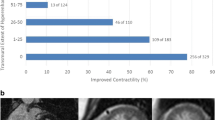

ROC curve analysis for the prediction of adverse LV remodeling after AMI at 6-month follow-up revealed that ECVinfarct and infarct size by LGE were the best predictors with AUCs of 0.843 and 0.789 (p < 0.01 for both), respectively (Table 3 and Fig. 4). ECVinfarct resulted in good sensitivity (0.86; 95% CI: 0.47–0.99) and specificity (0.85; 95% CI: 0.72–0.92). Infarct size by LGE also had a good sensitivity of 0.82 (95% CI: 0.51–0.96) and specificity of 0.74 (95% CI: 0.60–0.84). Native T1infacrt had the lowest AUC of 0.549 (p = 0.668) and was inferior to edema size by T2w (AUC = 0.720; p < 0.05) and native T2infarct (AUC = 0.766; p < 0.01) in predicting adverse LV remodeling. Additionally, the predictive performance of CMR parameters in the involved segments based on the AHA bull’s eye model was also assessed by ROC curve analysis. The findings resulted in a cutoff value of 34% for ECV (AUC = 0.653; p < 0.01) and 66 ms for native T2 relaxation times (AUC = 0.686; p < 0.01) in the involved segments for predicting adverse LV remodeling at 6-month follow-up (Table S1). The AUCs of cardiac biomarkers were 0.762 (p < 0.01) for peak CK, and 0.624 (p = 0.269) for peak CK-MB (Table 3).

Receiver-operating characteristic curve analysis for the prediction of adverse LV remodeling at 6 months following AMI with mapping (a) and standard CMR (b). ECVinfarct and infarct size by LGE were the best predictors of adverse LV remodeling with AUCs of 0.843 (p < 0.01) and 0.789 (p < 0.01), respectively. Native T1infarct had the lowest AUC of 0.549 (p = 0.668) and was inferior to edema size by T2-weighted (AUC = 0.720; p < 0.05) and native T2infarct (AUC = 0.766; p < 0.01) in predicting adverse LV remodeling. AMI, acute myocardial infarct; AUC, area under the curve; ECV, extracellular volume; LV, left ventricular